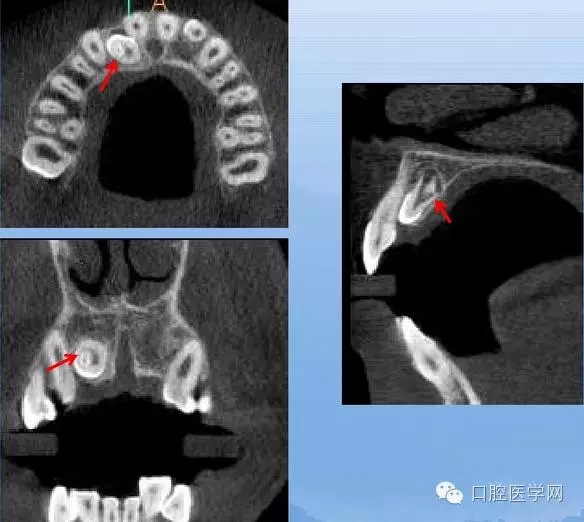

牙中牙

X線表現(xiàn):舌側(cè)窩陷入過深,形似一小牙包于牙髓中。